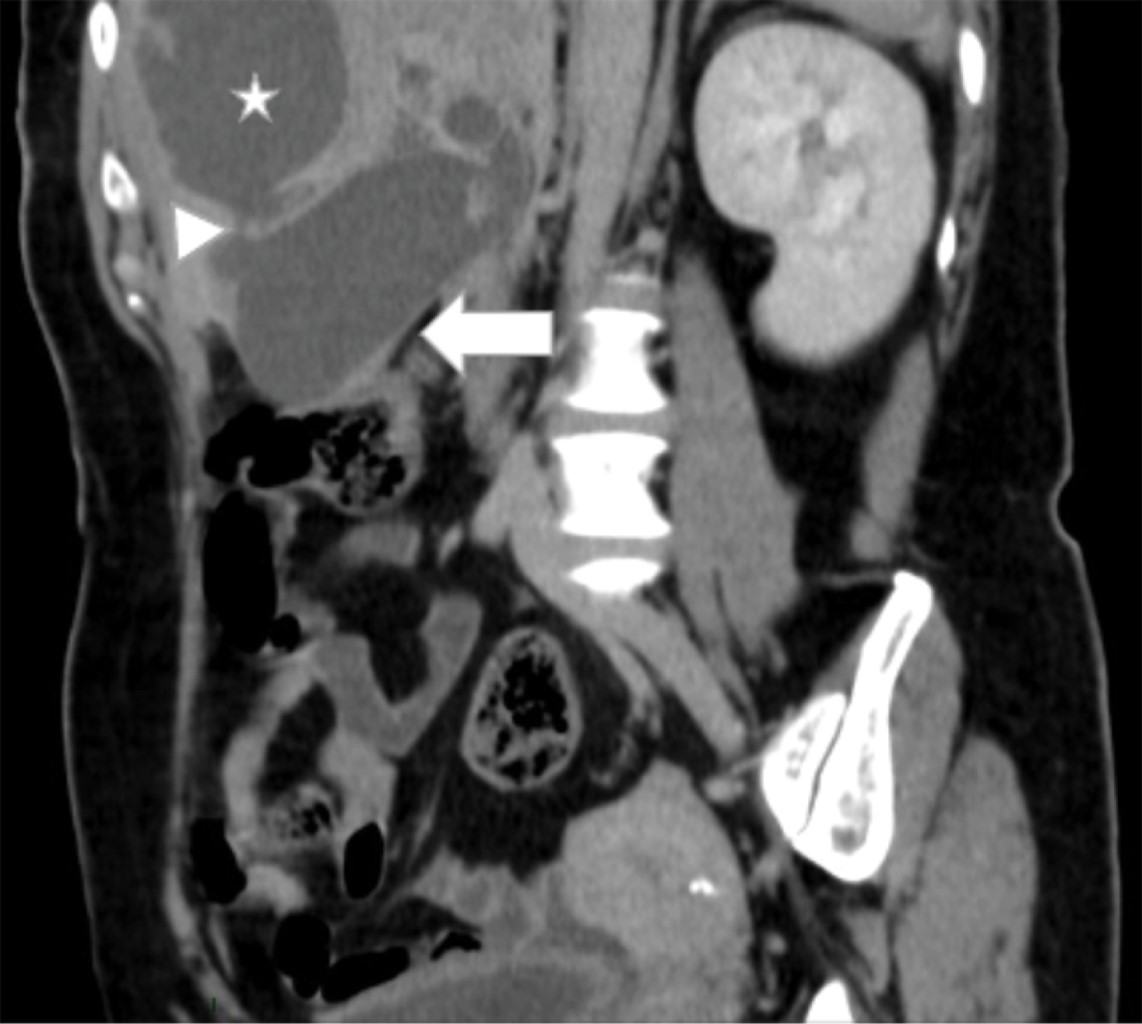

Se trata de paciente femenino de 55 años de edad quien acudió al servicio de urgencias con un cuadro de un mes de evolución caracterizado por dolor abdominal localizado en epigastrio e hipocondrio derecho, irradiado a región interescapular, mismo que fue aumentando, por lo que decidió acudir con facultativo quien inició manejo homeopático; sin embargo, no presentó mejoría, por lo que acudió al servicio de urgencias de nuestra unidad hospitalaria donde se registraron los siguientes signos vitales: TA (tensión arterial) 114/76 mmHg, Fc (frecuencia cardiaca) 124 lpm, Fr (frecuencia respiratoria) 16 rpm, temperatura 36 oC. Al interrogatorio la paciente negó la presencia de fiebre, náusea, vómito o presencia de evacuaciones disminuidas en consistencia. Para su abordaje se solicitaron laboratorios generales, de los cuales destacan la presencia de leucocitosis (12,300 mm3), elevación de fosfatasa alcalina y GGT (315 y 268 U/l respectivamente); se solicitó una tomografía computarizada de abdomen con contraste intravenoso (Figuras 1, 2 y 3) que evidenció la presencia de vesícula biliar con litos en su interior, impactados y ruptura intrahepática, además de un absceso intrahepático en segmentos IV y V (Figura 2).